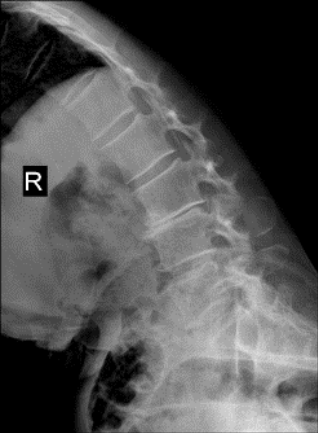

神经脊柱外科主任

主任医师邵世坤接诊后

通过详细查体和病情评估

明确老胡这病

属于巨大脱垂型腰椎间盘突出

压迫局部神经引起剧痛

同时伴有腰椎不稳

邵世坤用椎间孔镜技术

在老胡的脊柱自然空隙(椎间孔)里

置入一个直径不足1cm的通道

直达椎间盘病灶